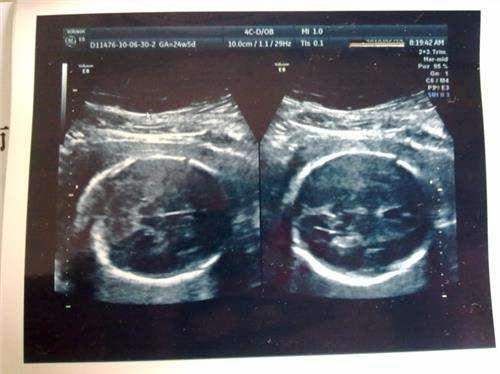

5、胎儿数量

这个道理很简单,怀两个孩子或者更多胎的孕妈,身体的营养要供给给两个甚至更多的孩子,哪怕是营养再充足,每个孩子获取的营养有限,再加上母体子宫的位置有限,一般胎儿会比单胎的要小一些。所以,如果是多胞胎孕妈,那营养补充要更重视,才能满足胎宝宝的需求。